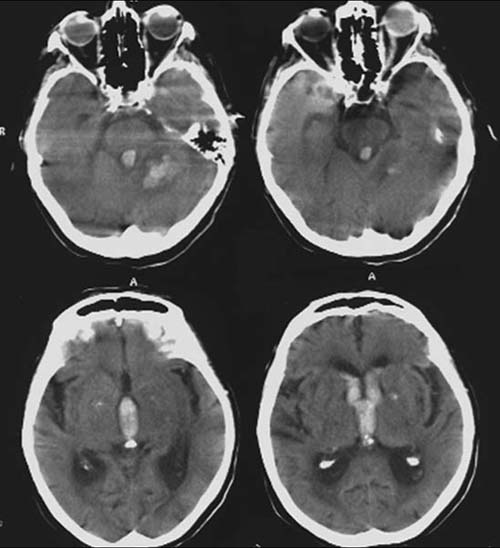

CCT nativ (ohne Kontrastmittel).

Hyperdense

(60-80HE) Raumforderung in der linken Kleinhirnhemisphäre mit perifokaler

Hyperdensivität.

Hyperdenser

Verhalt im gesamten Ventrikelsystem.

Verstrichene

Gyri und Sulci der linken Kleinhirnhemisphäre.

Im Seitenvergleich hyperdenser

Glaskörper links.

Hypertensive

Hirnmassenblutung der Kleinhirnhemisphere links und perifokalem

Ödem.

Einblutung ins Ventrikelsystem

Hirnödem v.a. der linken Kleinhirntonsille

Glaskörperblutung